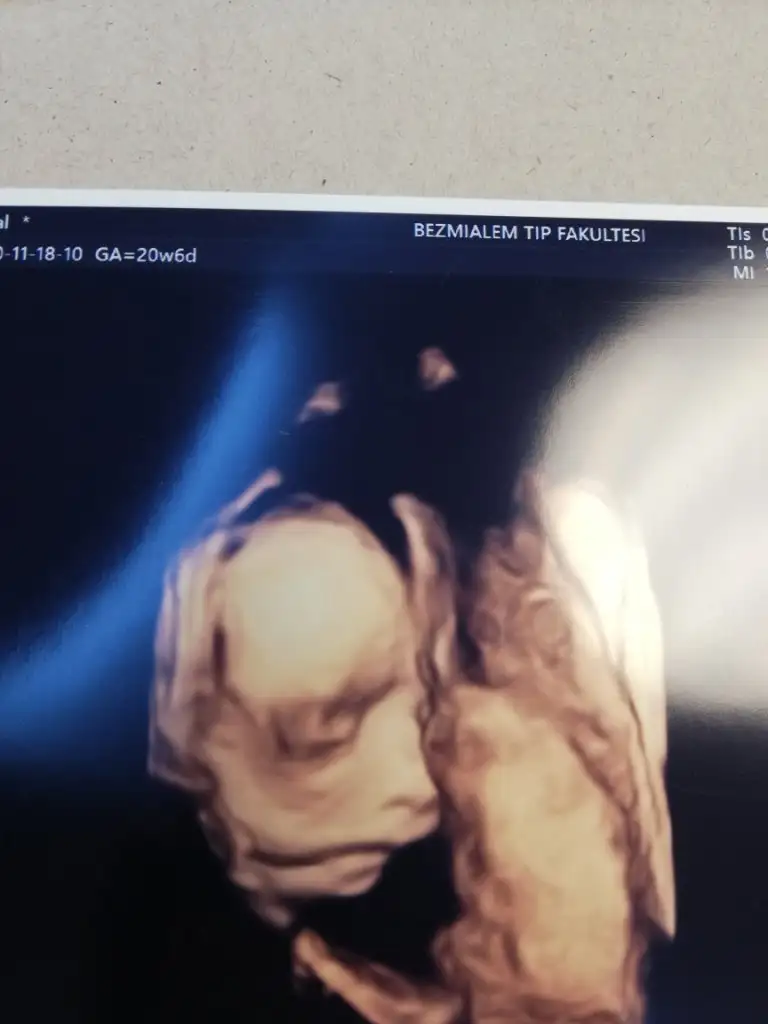

Ayrıntılıyı yaptırdık bugün .. Şükür herşey yolunda Doktor asistana tek tek saydıkça normal dedikçe şükür ettim gözlerim doldu.. 368 gr olmuş 24 cm dedi gayet güzel gelişimi ...Renkli foto da aldık ablası görsün diye.. Sürekli hareket halinde olduğundan en netlerini vermeye çalıştı..Down sendromu riskini %1 bile görmüyorum ama doktorunuzla genetik testini yine de konuşursunuz dedi. Bana kalırsa gerek yok dedi..

Evet canım Mehmet Serdar Kütük 450 tl ödedim ..Kendi doktorum tavsiye etmişti. Gayet ilgili güler yüzlü bir doktor.. Tavsiye ederim.Maşallah kuzucuğa herşeyin yolunda olmasına sevindim. Birşey sormak istiyorum Bezmiâlem de yaptırmışsın perinatolog mu baktı doktorunuz kimdi? Ücret olarak ne kadar ödediniz?